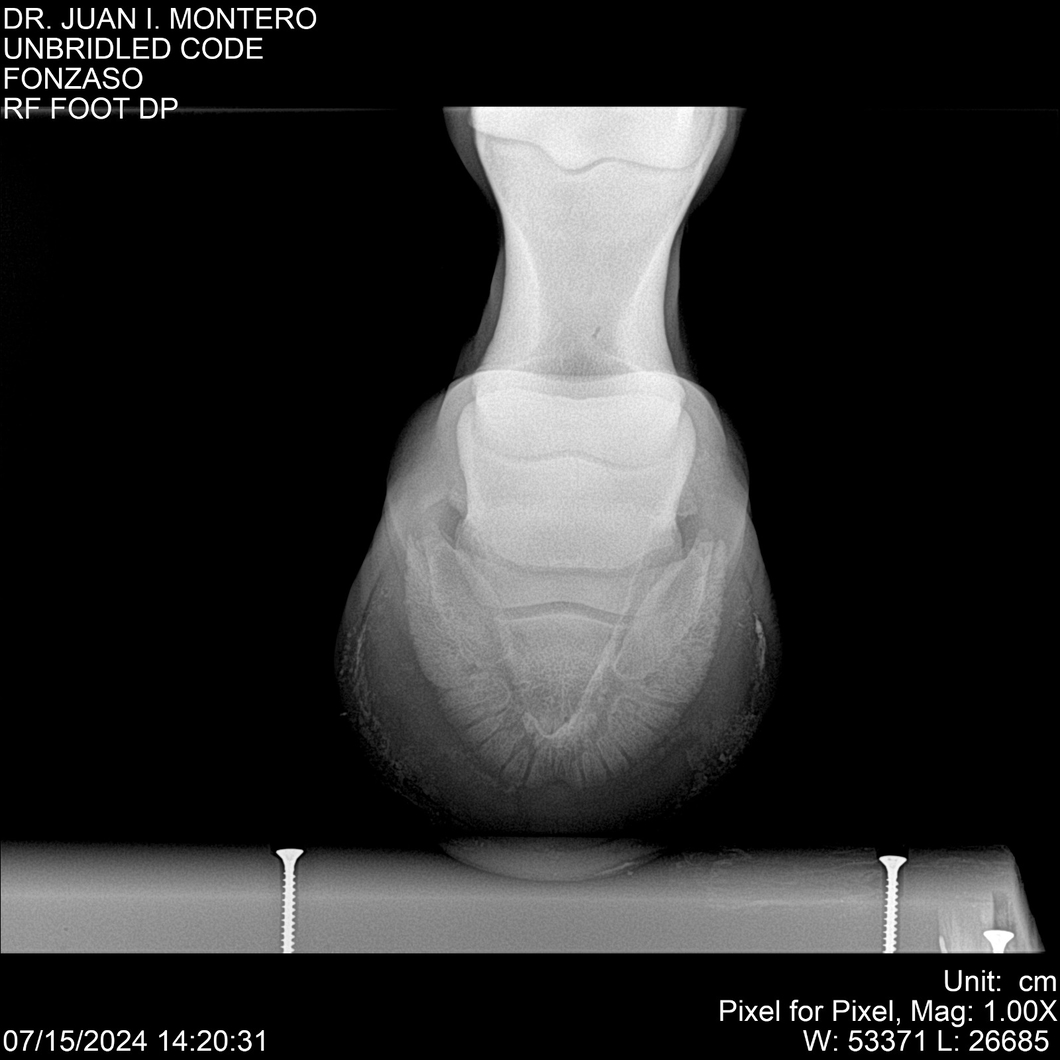

• Empresa: Abelenda N. R., Walter Hugo